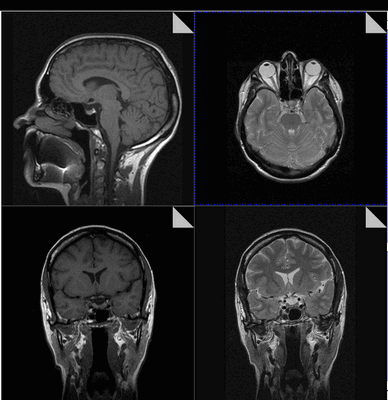

МРТ гипофиза до и после операции по удалению макроаденомы гипофиза

МРТ гипофиза при краниофарингиоме: сканы в разных проекциях